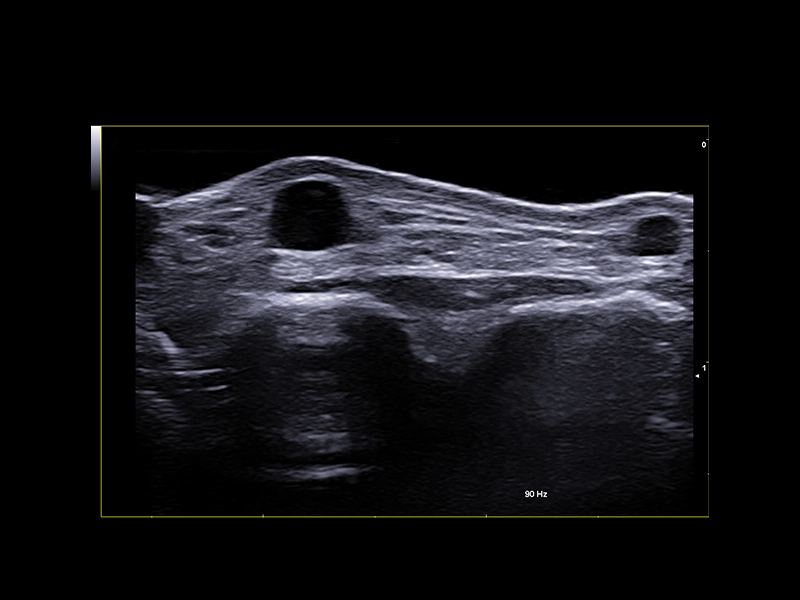

MyLab™9 Platform - High Frequency MSK Imaging with HD Zoom

MyLab™9 Platform - High Frequency MSK Imaging with HD Zoom